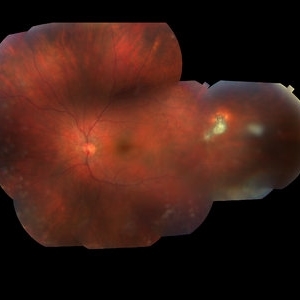

Color fundus montage of an 13-year-old female with arteriovenous malformation (Wyburn Mason Racemose Angiomatosis) affecting her right eye. The retinal arteriovenous malformation appears to be stable. She presented with NLP in the eye, strabismus, and peripheral retinal ischemia. She is at risk for neovascular complications; however, she is currently being treated with Sirolimus. Since she is on this systemically, there is no need to perform intraocular anti-VEGF injections or PRP laser. She also presented with optic atrophy affecting her left eye, secondary to chiasmal involvement of arteriovenous malformation. She has had a potential progressive visual field loss involving the temporal aspect of her visual field from the left eye. There is sector optic atrophy. Presumably, this is due to a compressive effect of her arteriovenous malformation on the nasal nerve fiber layer (corresponding to the temporal visual field) crossing to the right occipital cortex at the chiasm.

Photographer: Olivia Rainey

Imaging device: Topcon 50dx

Condition/keywords: arteriovenous malformation, color fundus photograph, color photo, montage, peripheral ischemia, Sirolimus